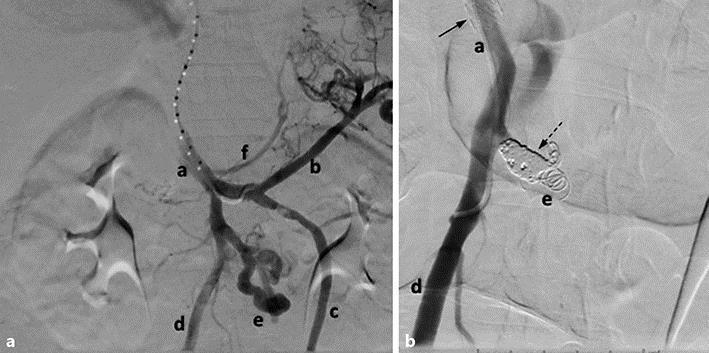

Duodenal variceal bleeding is an uncommon complication of portal hypertension that can easily go unrecognized and reach mortality rates as high as 40%. Cirrhosis is the most common cause of duodenal varices. In most cases, duodenal varices occur concomitantly with esophageal varices, further complicating identification with initial endoscopy. Although many modalities have been explored with respect to management and treatment approaches, guidelines have yet to be established owing to the infrequency in which bleeding occurs from ectopic duodenal varices. We present a case of massive duodenal variceal hemorrhage that highlights the complexity of initial diagnosis and ultimately required a transesophageal intrahepatic portosystemic shunt with coil embolization for control of bleeding.

十二指肠静脉曲张出血是门静脉高压症的一种罕见并发症,很容易被忽视,死亡率高达40%。肝硬化是十二指肠静脉曲张最常见的病因。在大多数情况下,十二指肠静脉曲张与食管静脉曲张同时出现,这使得初次内镜检查时的鉴别更加复杂。尽管在管理和治疗方法方面已经探索了多种方式,但由于异位十二指肠静脉曲张出血的发生率较低,尚未制定相关指南。我们报告一例大量十二指肠静脉曲张出血的病例,该病例突出了初始诊断的复杂性,最终需要行经食管肝内门体分流术并联合弹簧圈栓塞来控制出血。